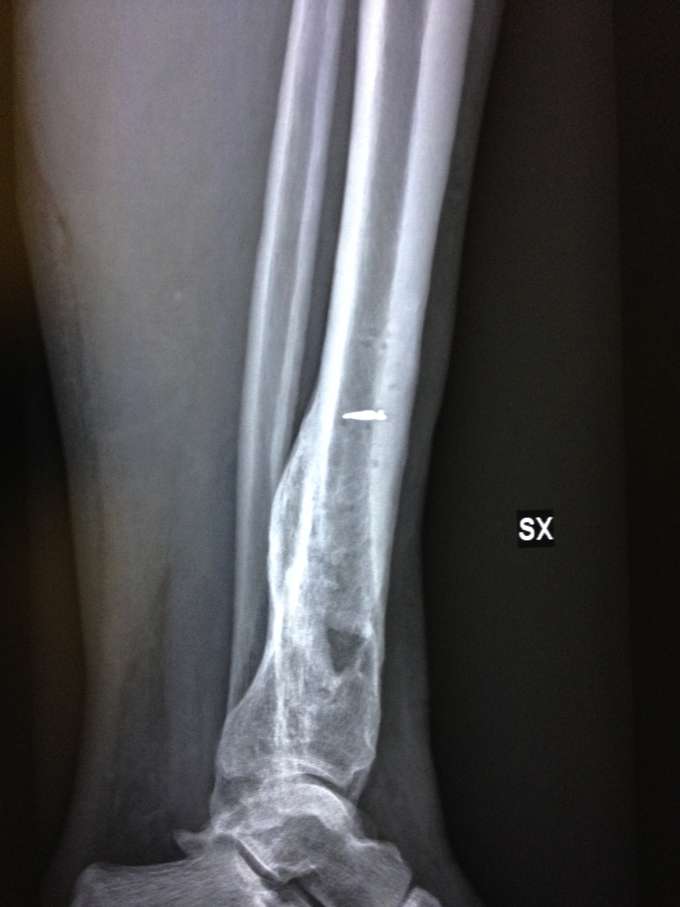

Ecco qualche foto:

Radiografie: si noti il buco nero che è il focolaio dell'infezione che ha mangiato l'osso (foto 1) e il callo osseo che si stacca a causa dell'osteomielite (foto 2)